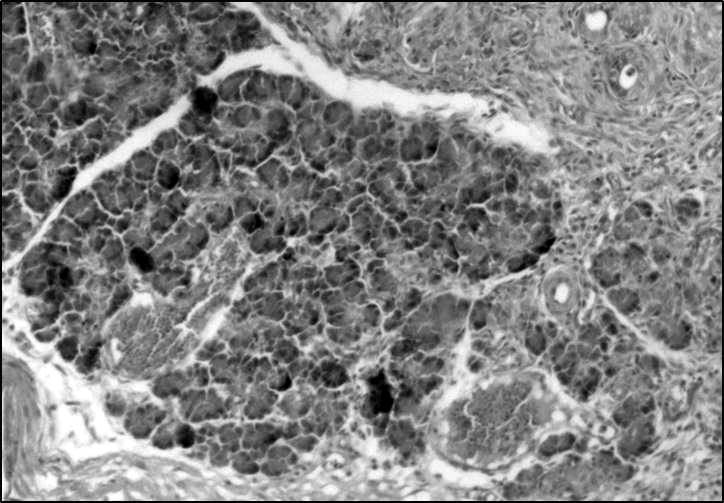

Рис. 2. Поджелудочная железа, жизнеспособный панкреатический островок, 7-е сутки, экспериментальная группа с соединением «L-17». Окр. гематоксилином и эозином, ув. ×200

В экспериментальной группе с ОПП на фоне введения соединения «L-17» к 7-м суткам в поджелудочной железе выявлялись очаговые некрозы части долек поджелудочной железы без тенденции к слиянию и очаговые некрозы в парапанкреатической клетчатке с формированием лейкоцитарного вала. В перифокальной области определялись функционально активные фибробласты с формированием грануляционной ткани. Обнаружена пролиферация протокового эпителия с формированием множественных мелких протоков. В зонах, примыкающих к некрозу, визуализировались жизнеспособные островки Лангерганса (в 7 срезах из 10) (рис. 2). В легких определялось полнокровие перибронхиальных сосудов, умеренная очаговая периваскулярная и перибронхиальная инфильтрация сегментоядерными лейкоцитами. Сформированные очаги пневмонии не выявлялись. В селезенке соотношение красной и белой пульпы соответствовало интактным животным, определялось незначительное нарушение зональности лимфоидных фолликулов без признаков лимфопении. В печени выявлялась умеренная лимфоидная инфильтрация портальных трактов и расширение синусоидальных сосудов, очагов абсцедирования или некрозов не выявлено. В почках структурных изменений не было, определялось только полнокровие сосудов и капилляростаз в синусоидальных сосудах коркового вещества, воспалительных изменений не было. В правых отделах сердца выявлялся капилляростаз и полнокровие подэпикардиальных сосудов с небольшим интерстициальным отеком.